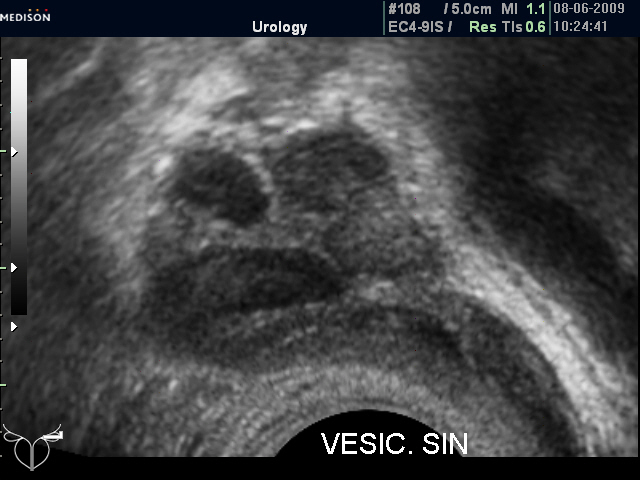

И еще "вдогонку", из вчерашнего. Правый СП 19,7 мм, левый - 23,3 мм.

ТРУЗИ левого СП